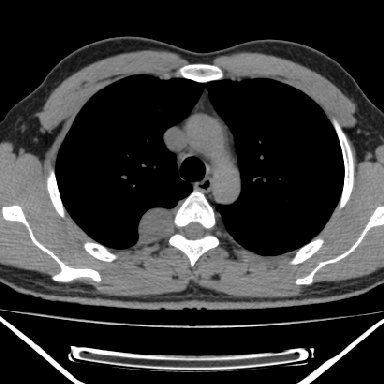

m 30 右胸痛10年

病灶与椎间孔间存在脂间隙,病灶较大,椎间无明显异常改变,与胸膜移行处可见尾状影,考虑胸膜肿瘤,以良性间皮瘤可能性大

病灶最大径线处于肋间隙,不排除起源于肋神经源性肿瘤

右上后纵隔旁软组织肿块影,与肺界面光滑,与胸壁呈钝角相交,提示肺外病变。位于肋骨下缘,边缘清楚,呈三角样指向与右侧椎间孔,但并示进入椎间孔;与对侧神经根对比,属同一走行方向。

考虑后纵膈良性肿瘤,神经源性肿瘤可能大。

鉴别:胸膜来源肿瘤。影像表现虽有肺外征象,但无胸水等相应佐证;再者,病史前10年,超长,与胸膜肿瘤不太吻合。

良性胸膜间皮瘤可能性大,神经源性肿瘤可能性小,因为没有见到有瘤体组织伸入神经孔内!

右上后纵隔脊柱旁见长椭圆形肿块,边界光整,与胸壁呈钝角。周围骨质未见异常。

考虑、1、后纵隔神经源性肿瘤;

2、不除外单发胸膜间皮瘤。